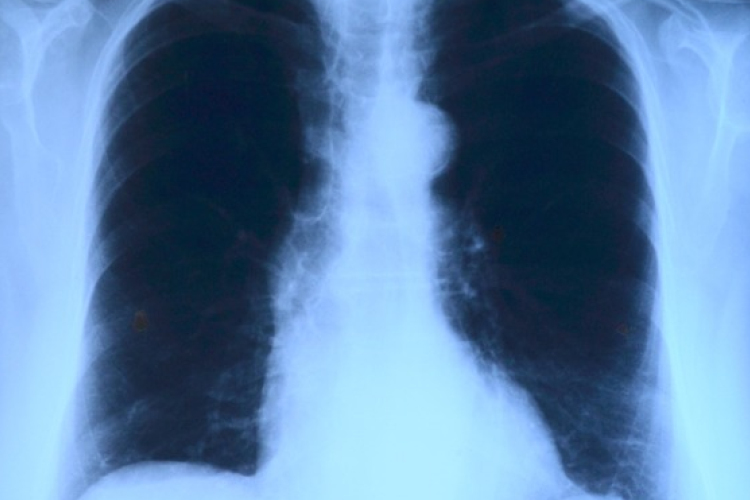

Elvégezték az országban az első tüdőverőér-tágítást

Az országban elsőként a Debreceni Egyetem Klinikai Központjában végeztek tüdőverőér-tágítást - közölte a felsőoktatási intézmény sajtóirodája kedden az MTI-vel.